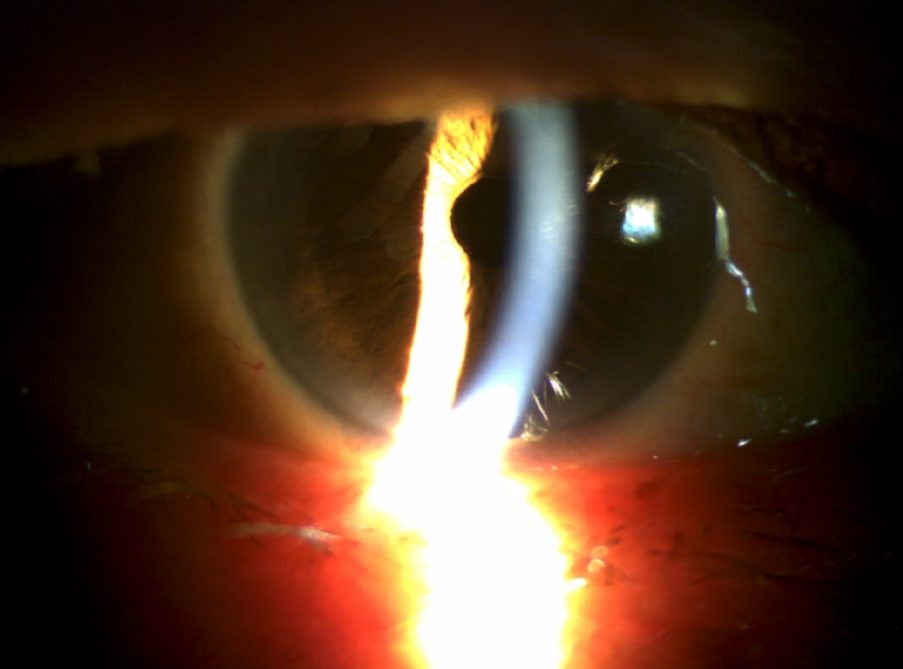

핵백내장 수술

71세 남성 환자 사례

수술 1개월 후 나안시력 0.9

54세 남성 환자 사례

수술 8개월 후 나안시력 0.9

수술 전

수술 후

※ 해당 이미지는 본원에서 직접 촬영한 사진입니다.